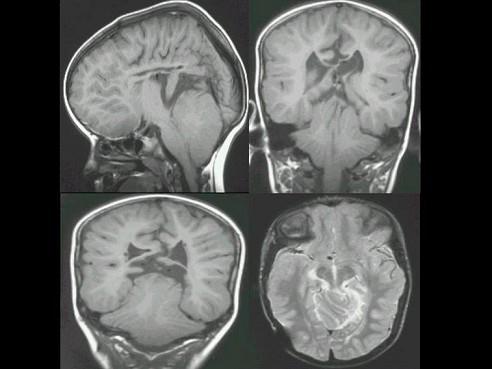

问题 男,3岁,根据所示图像,最可能的诊断?(?)

选项 A.脑室畸形 B.小脑畸形 C.脑干畸形 D.Chiari畸形 E.Dandy-Walker综合征

答案 D